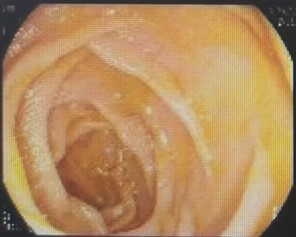

面对如此紧急的情况,干部保健病区冯建军主任联合消化内科赵刚副主任迅速启动了绿色通道,为刘爷爷进行了初步的稳定治疗,同时召集多学科专家进行紧急会诊。专家们一致决定先进行胃镜检查,了解患者既往手术方式,同时为可能的ERCP操作进行“探路”。后经胃镜检查,明确老人确实为“毕Ⅱ式远端胃部分切除”术后改变,内镜下反复寻找后,终于找到输入袢肠管以及十二指肠主乳头,同时为了后续手术时便于再次寻找,以一枚金属夹在十二指肠主乳头旁侧进行标记。

胃肠吻合口

输出袢肠管

输入袢肠管

十二指肠主乳头